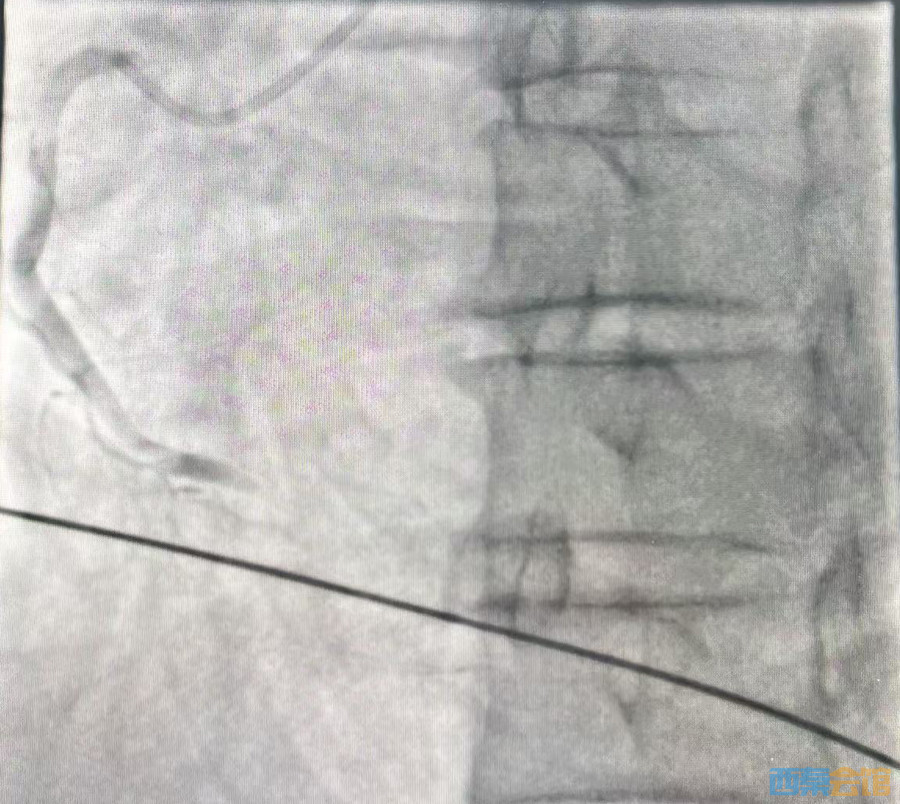

医生检查发现:郭先生是急性心肌梗死,心脏右冠状动脉的远端已经完全闭塞,没有任何血流通过;之后经手术植入心梗支架后,郭先生终于转危为安。

113.jpeg

右冠状动脉的远端完全闭塞,没有任何血流通过